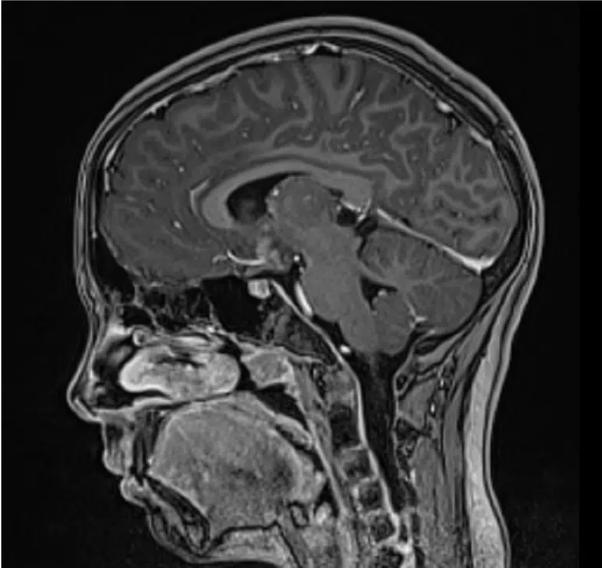

植入中心静脉导管。辅助化疗包括两个疗程的卡铂/依托泊苷,交替两个疗程的异环磷酰胺/依托泊苷。这些疗程每隔21天进行一次;只有第二个疗程因血液毒性而推迟。四个疗程化疗后的脑部MRI显示没有残留肿瘤(图2)。在后期,患者接受了放射治疗,接受了全脑室照射和肿瘤床照射,总剂量为24gy(15次分割,每次分割剂量为1.6 Gy)。

图2、化疗结束后的脑部磁共振成像。 磁共振成像显示没有残留肿瘤